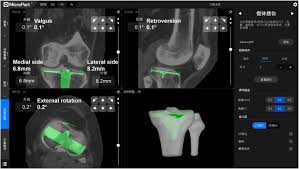

Verification And Clinical Translation Of A Newly Designed Skywalker Robot For Total Knee Arthroplasty A Prospective Clinical Study Sciencedirect